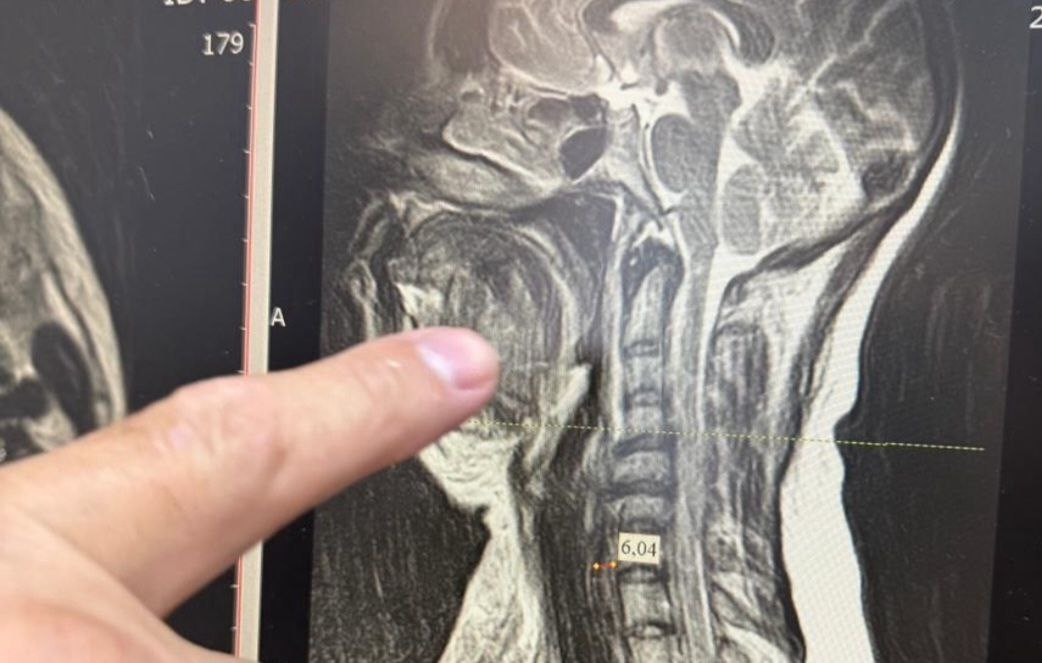

Медики столкнулись с одной из самых сложных форм осложнения – двусторонней флегмоной окологлоточного пространства, которая при отсутствии своевременного лечения в большинстве случаев заканчивается летальным исходом. Специалисты стали готовить женщину к экстренной операции. Из-за сильного отека тканей шеи невозможно было вставить трубку для дыхательного наркоза, поэтому работали через трахею.

Челюстно-лицевой хирург Шахбан Мисриев установил около восьми дренажей. Три дня пациентка провела в реанимационном отделении, подключенной к аппарату ИВЛ.